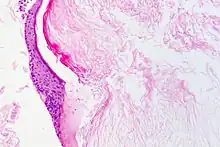

Le cholestéatome est une forme d'otite chronique avec présence d'épithélium pavimenteux stratifié dans l'oreille moyenne. Cet épithélium desquame et se kératinise (structure histologique de l'épiderme), et peut provoquer l'érosion voire la destruction des structures contenues dans et autour de l'oreille moyenne ( Histopathologie du cholestéatome)[1],[2].

Il se fait par visualisation du conduit auditif et du tympan (otoscopie). Il se manifeste par la présence d'une excroissance squameuse, le plus souvent à la partie postéro supérieure du tympan[7]. Le scanner crânien permet de visualiser l'extension et les éventuelles destructions osseuses.L'histopathologie post-opératoire est indispensable pour confirmer la nature de la lésion et celles qui lui sont associées.